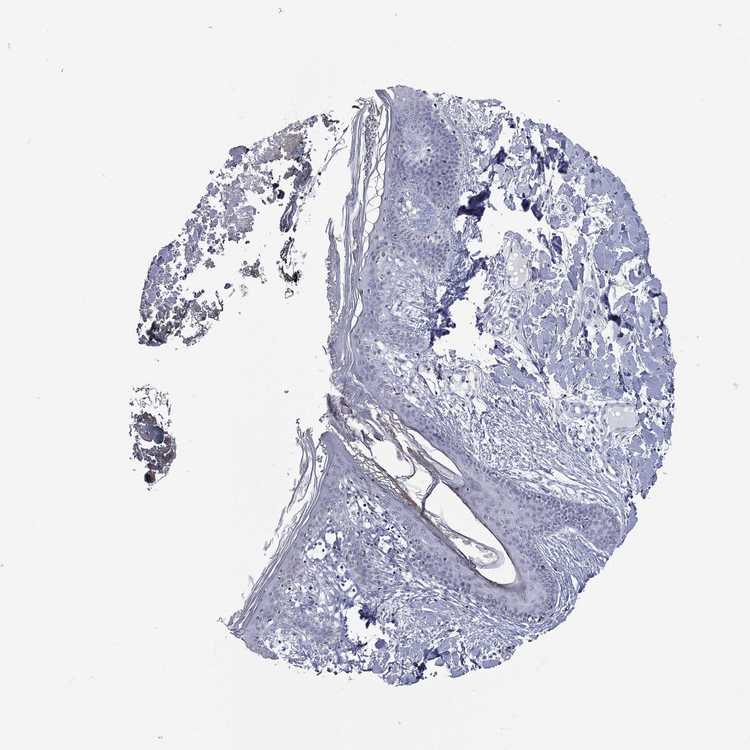

SKIN 2 - Antibody stainingi

Antibody staining in the annotated cell types in the current human tissue is reported as not detected, low, medium, or high, based on conventional immunohistochemistry profiling in selected tissues. This score is based on the combination of the staining intensity and fraction of stained cells.

Each image is clickable and will lead to virtual microscopy that enables deeper exploration of all samples and also displays staining intensity scores, fraction scores and subcellular localization as well as patient and tissue information for each sample.

Antibody HPA076284

Epidermal cells Low